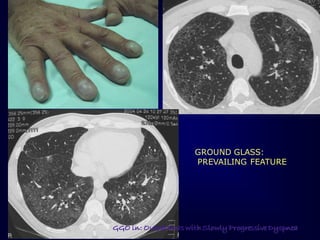

GROUND GLASS:

PREVAILING FEATURE

ERS 2008

GGO in: Outpatients with Slowly Progressive Dyspnea

DIP

Typically: subpleural /lower lung zones

Reticulation seen in ~40-50%

Honeycombing NOT significant

• 61.

GROUND GLASS: PREVAILING FEATURE ERS2008 GGO in: Outpatients with Slowly Progressive Dyspnea

• 62.

DIP Typically: subpleural /lowerlung zones Reticulation seen in ~40-50% Honeycombing NOT significant ERS 2008